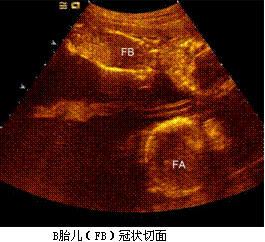

孕妇,30岁,孕2产0孕22周。超声(孕12周):宫内妊娠,单绒毛膜囊双羊膜囊双活胎,A胎儿NT0.32cm,B胎儿NT0.12cm。孕22周复查超声如下图。

孕妇,30岁,孕2产0孕22周。超声(孕12周):宫内妊娠,单绒毛膜囊双羊膜囊双活胎,A胎儿NT0.32cm,B胎儿NT0.12cm。孕22周复查超声如下图。<br /><img s